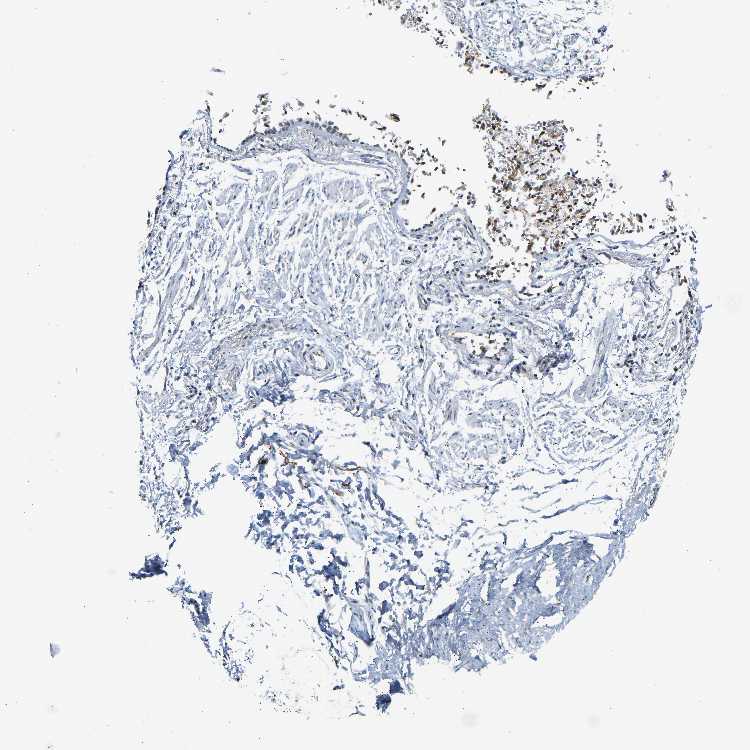

ADIPOSE TISSUE - Antibody stainingi

Antibody staining in the annotated cell types in the current human tissue is reported as not detected, low, medium, or high, based on conventional immunohistochemistry profiling in selected tissues. This score is based on the combination of the staining intensity and fraction of stained cells.

Each image is clickable and will lead to virtual microscopy that enables deeper exploration of all samples and also displays staining intensity scores, fraction scores and subcellular localization as well as patient and tissue information for each sample.

Antibody HPA019824Antibody CAB015201

Adipocytes Not detectedMedium